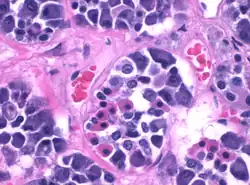

Durante décadas los tipos de células se clasificaron según su afinidad por las tinciones en: acidófilas, basófilas y cromófobas, estas últimas no se tiñen. Esta clasificación morfológica no aportaba información significativa sobre su actividad secretora. En la actualidad, se cuenta con técnicas de inmunohistoquímica, y se han podido identificar cinco tipos celulares principales que son secretores: células somatotropas, células lactotropas, células corticotropas, células gonadotropas y células tirotropas.[2]

Las células Somatotrofas[6] tienen unos grandes gránulos acidófilos, y se tiñen de color naranja intenso con eosina. Se encuentra gran cantidad de ellas en la parte distal de la adenohipófisis. Secretan somatotropina u hormona del crecimiento. Tienen un núcleo central, mitocondrias en bastón y un abundante retículo endoplásmico rugoso.

Las células corticotropas[8] son basófilas, redondas u ovoides, con un núcleo excéntrico y pocos orgánulos. Secretan hormona adrenocorticotrópica (ACTH) y hormona lipotrópica o lipotropina (LPH) ). Sus gránulos se excretan con el estímulo de la hormona liberadora de corticotropina (CRH).

Las células Gonadotrofas[9] son basófilas, redondas, con abundante retículo endoplásmico rugoso y abundantes mitocondrias. Secretan las gonadotropinas LH y FSH. Aún no ha podido confirmarse si existen dos poblaciones de células gonadótropas: unas que producen la hormona luteinizante[10] y otras, la hormona foliculoestimulante, o si una misma célula produce ambas hormonas en diferentes fases de un mismo ciclo secretor.[cita requerida]

Las células Tirotrofas[11] son basófilas. Se encuentran cerca de los cordones, a cierta distancia de los sinusoides. Se distinguen por sus gránulos pequeños de tirotropina (TSH). También estimulan la liberación de prolactina.